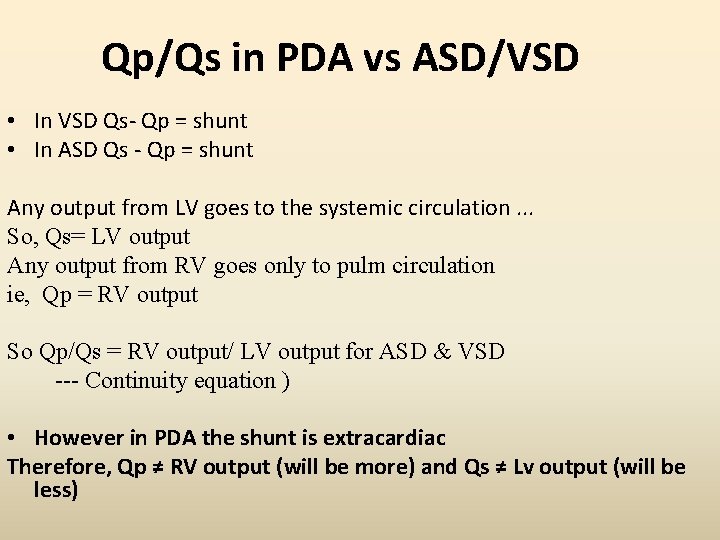

Qp/Qs in PDA vs ASD/VSD • In VSD Qs- Qp = shunt • In ASD Qs - Qp = shunt Any output from LV goes to the systemic circulation. . . So, Qs= LV output Any output from RV goes only to pulm circulation ie, Qp = RV output So Qp/Qs = RV output/ LV output for ASD & VSD --- Continuity equation ) • However in PDA the shunt is extracardiac Therefore, Qp ≠ RV output (will be more) and Qs ≠ Lv output (will be less)